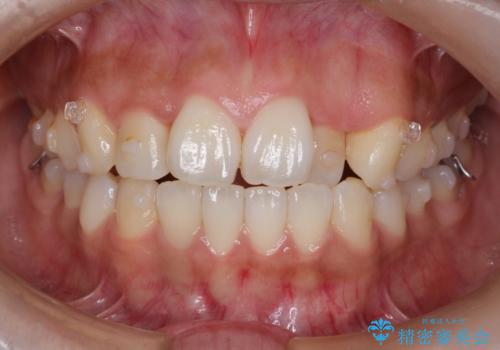

【引っ込んだ前歯が気になる、真ん中の線も揃えたい】インビザライン症例

- 前歯の歯並びの改善を希望され来院された患者様です。

初診時の歯並びの状態としては、上下ともに全体に及ぶの中等度のがたつき(叢生)があり、全特に左上の前歯は1本だけ引っ込んでいる状態でした。

抜歯は行わず上顎の奥のスペースを利用して歯をスライドする方法の他に歯列弓の拡大やディスキング(歯と歯の間の隙間を作る処置)を行い叢生を改善しました。

歯の大きさの不揃いが原因の正中のズレは、ディスキング量を調整することで合わせました。